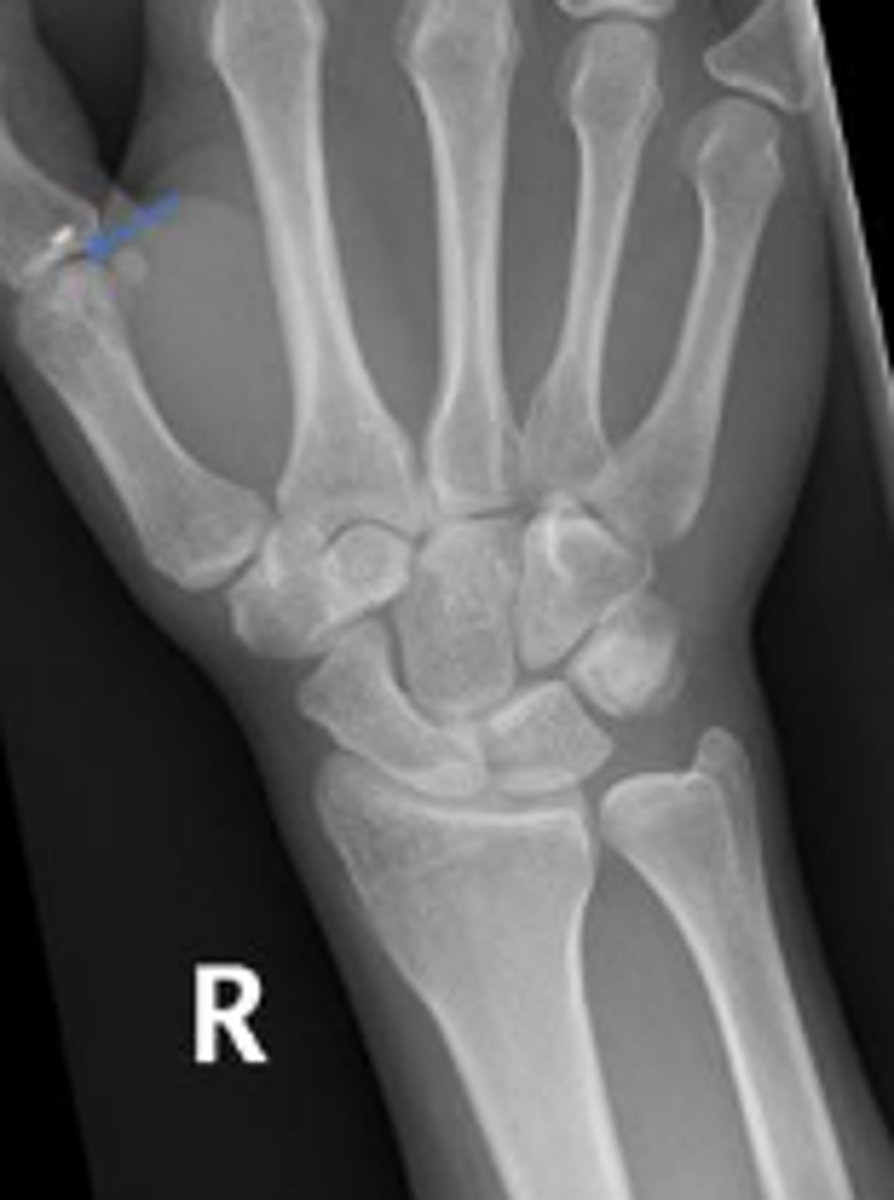

Medial oblique of the right wrist

What is the name of the radiographic view?

PA right wrist